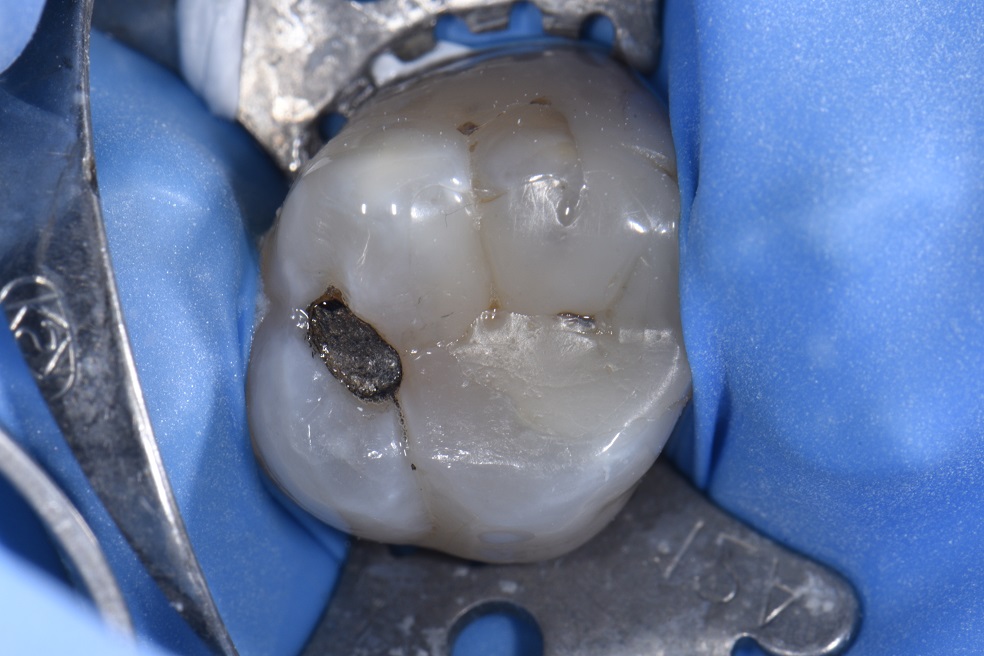

from wrigleyvilledental.com